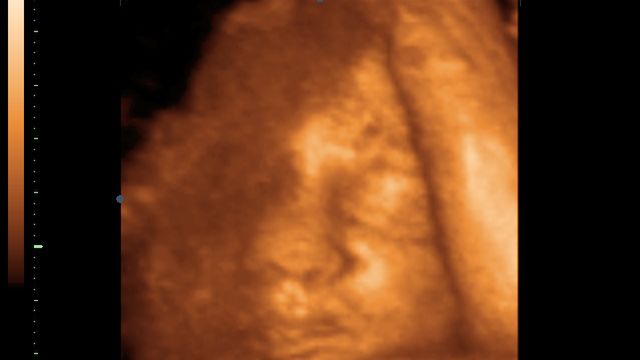

/ 2Płód w 40 tygodniu ciąży - przygotowanie ciała do porodu

Szyjka macicy rozluźnia się gotowa na poród